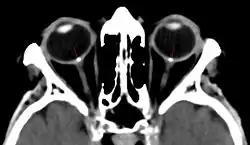

Комп'ютерну томографію (КТ) також використовують для візуалізації нерва. Перевагу над МРТ цей метод має у випадках підозр на стиснення нерва у зоровому каналі, оскільки краще візуалізує кісткову тканину. Загалом, у випадку травм з переломами кісток, коли є можливість ушкодження зорового нерва, КТ є методом вибору. Цей метод чутливий до кальцифікатів, тому його використання доцільне у випадку підозр на наявність друзів.[78][79]

Травми зорового нерва бувають прямими, коли внаслідок дії травматичного чинника безпосередньо порушується анатомічна цілісність нерва, та непрямими, коли проникнення безпосередньо не спричинило пошкодження нерва, проте його наслідки (гематома, набряк, тощо) ушкоджують нерв[104][105]. Серед усіх частин найбільшому ризику травматизації підлягає канальна частина нерва, оскільки вона знаходиться в обмеженому кісткою вузькому просторі. Очноямкова частина захищена жировою клітковиною, а внутрішньочерепна — кістками черепа та тканиною мозку, відповідно ці частини ушкоджуються рідше. Травматична нейропатія може виникнути як при локальному ушкодженні, так і при травмі голови.[106]